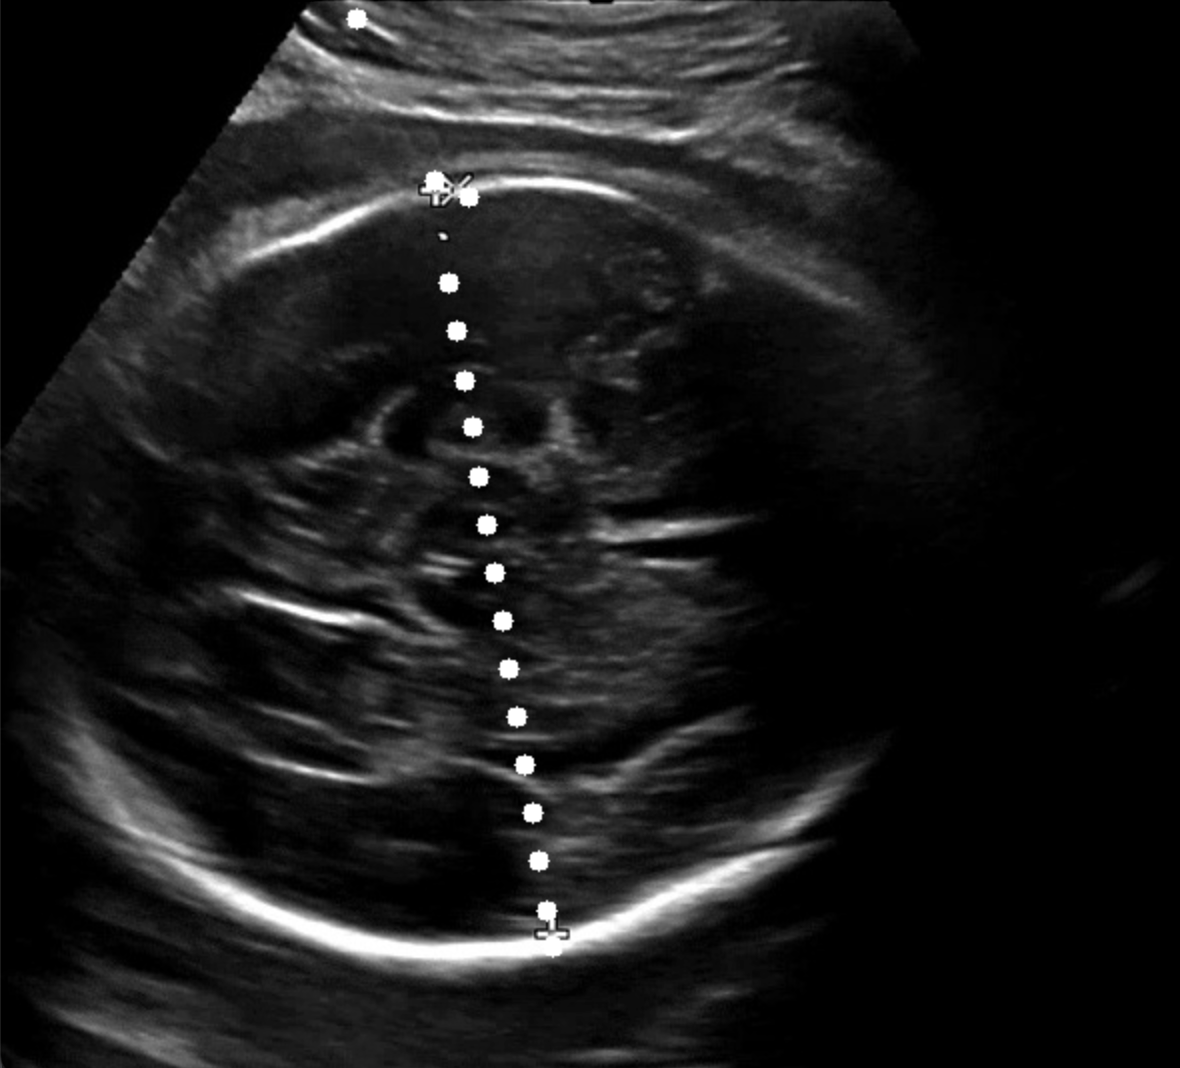

점선 패턴을 활용한 두개골 인식에서 대부분의 경우 안정적으로 좌표를 추출할 수 있었지만, 간혹 좌표값이 튀는 이상치 (outlier) 가 발생하는 사례를 확인했다. 이는 점선 패턴이 이미지의 특정 영역에서 명확히 인식되지 않거나, 노이즈로 인해 잘못된 좌표가 포함되는 경우였다. 아래 이미지와 같은 경우에서 좌표값이 연속되지 않고 불규칙하게 분포하거나, 특정 축(x 축 또는 y 축)을 기준으로 값이 급격히 변화하는 사례가 대표적이었다.

이를 보완하기 위해 좌표 클러스터링 (clustering) 기법을 도입했다. 우선, x 축을 기준으로 tolerance (허용 오차) 내에 위치한 점들을 하나의 클러스터로 그룹화하고, 각 클러스터의 크기를 비교하여 가장 큰 클러스터를 선택했다. 이렇게 선택된 클러스터는 가장 신뢰도가 높은 점선 패턴을 나타낸다고 가정했다. 이후, 선택된 클러스터의 좌표를 y 축 기준으로 정렬하여 점선 패턴을 복원했다. 그러나 단순히 x 축 기준으로 클러스터링한 결과에서도 문제는 여전히 존재했다. x 축 좌표는 유사하지만 y 축 좌표가 급격히 튀는 사례가 빈번하게 나타났기 때문이다. 이를 해결하기 위해 y 축 기준으로 동일한 클러스터링 과정을 추가적으로 적용했다. 즉, x 축과 y 축 모두에 대해 클러스터링을 진행함으로써, 튀는 좌표를 효과적으로 제거하고 점선 패턴의 연속성을 더욱 강화할 수 있었다.